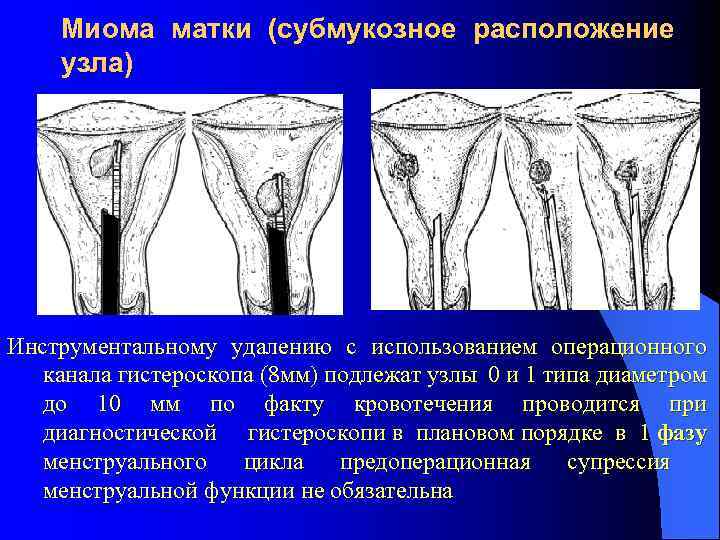

Миома матки (субмукозное расположение узла) резекционная технология

Миома матки (субмукозное расположение узла) Инструментальному удалению с использованием операционного канала гистероскопа (8 мм) подлежат узлы 0 и 1 типа диаметром до 10 мм по факту кровотечения проводится при диагностической гистероскопи в плановом порядке в 1 фазу менструального цикла предоперационная супрессия менструальной функции не обязательна